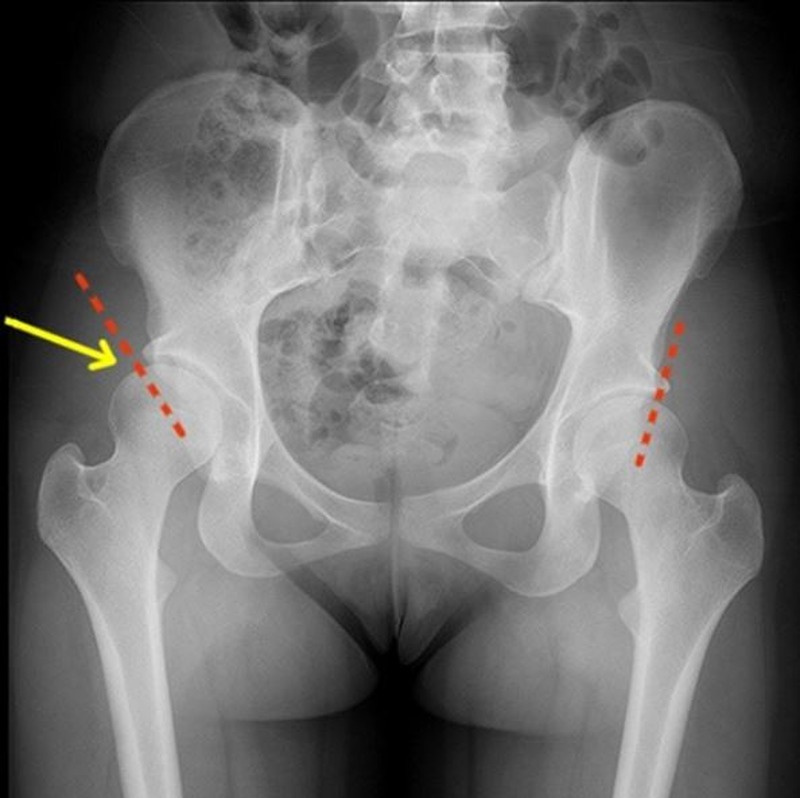

Рентген ТБС: Нормальные показатели

Раздел: Необычные решения